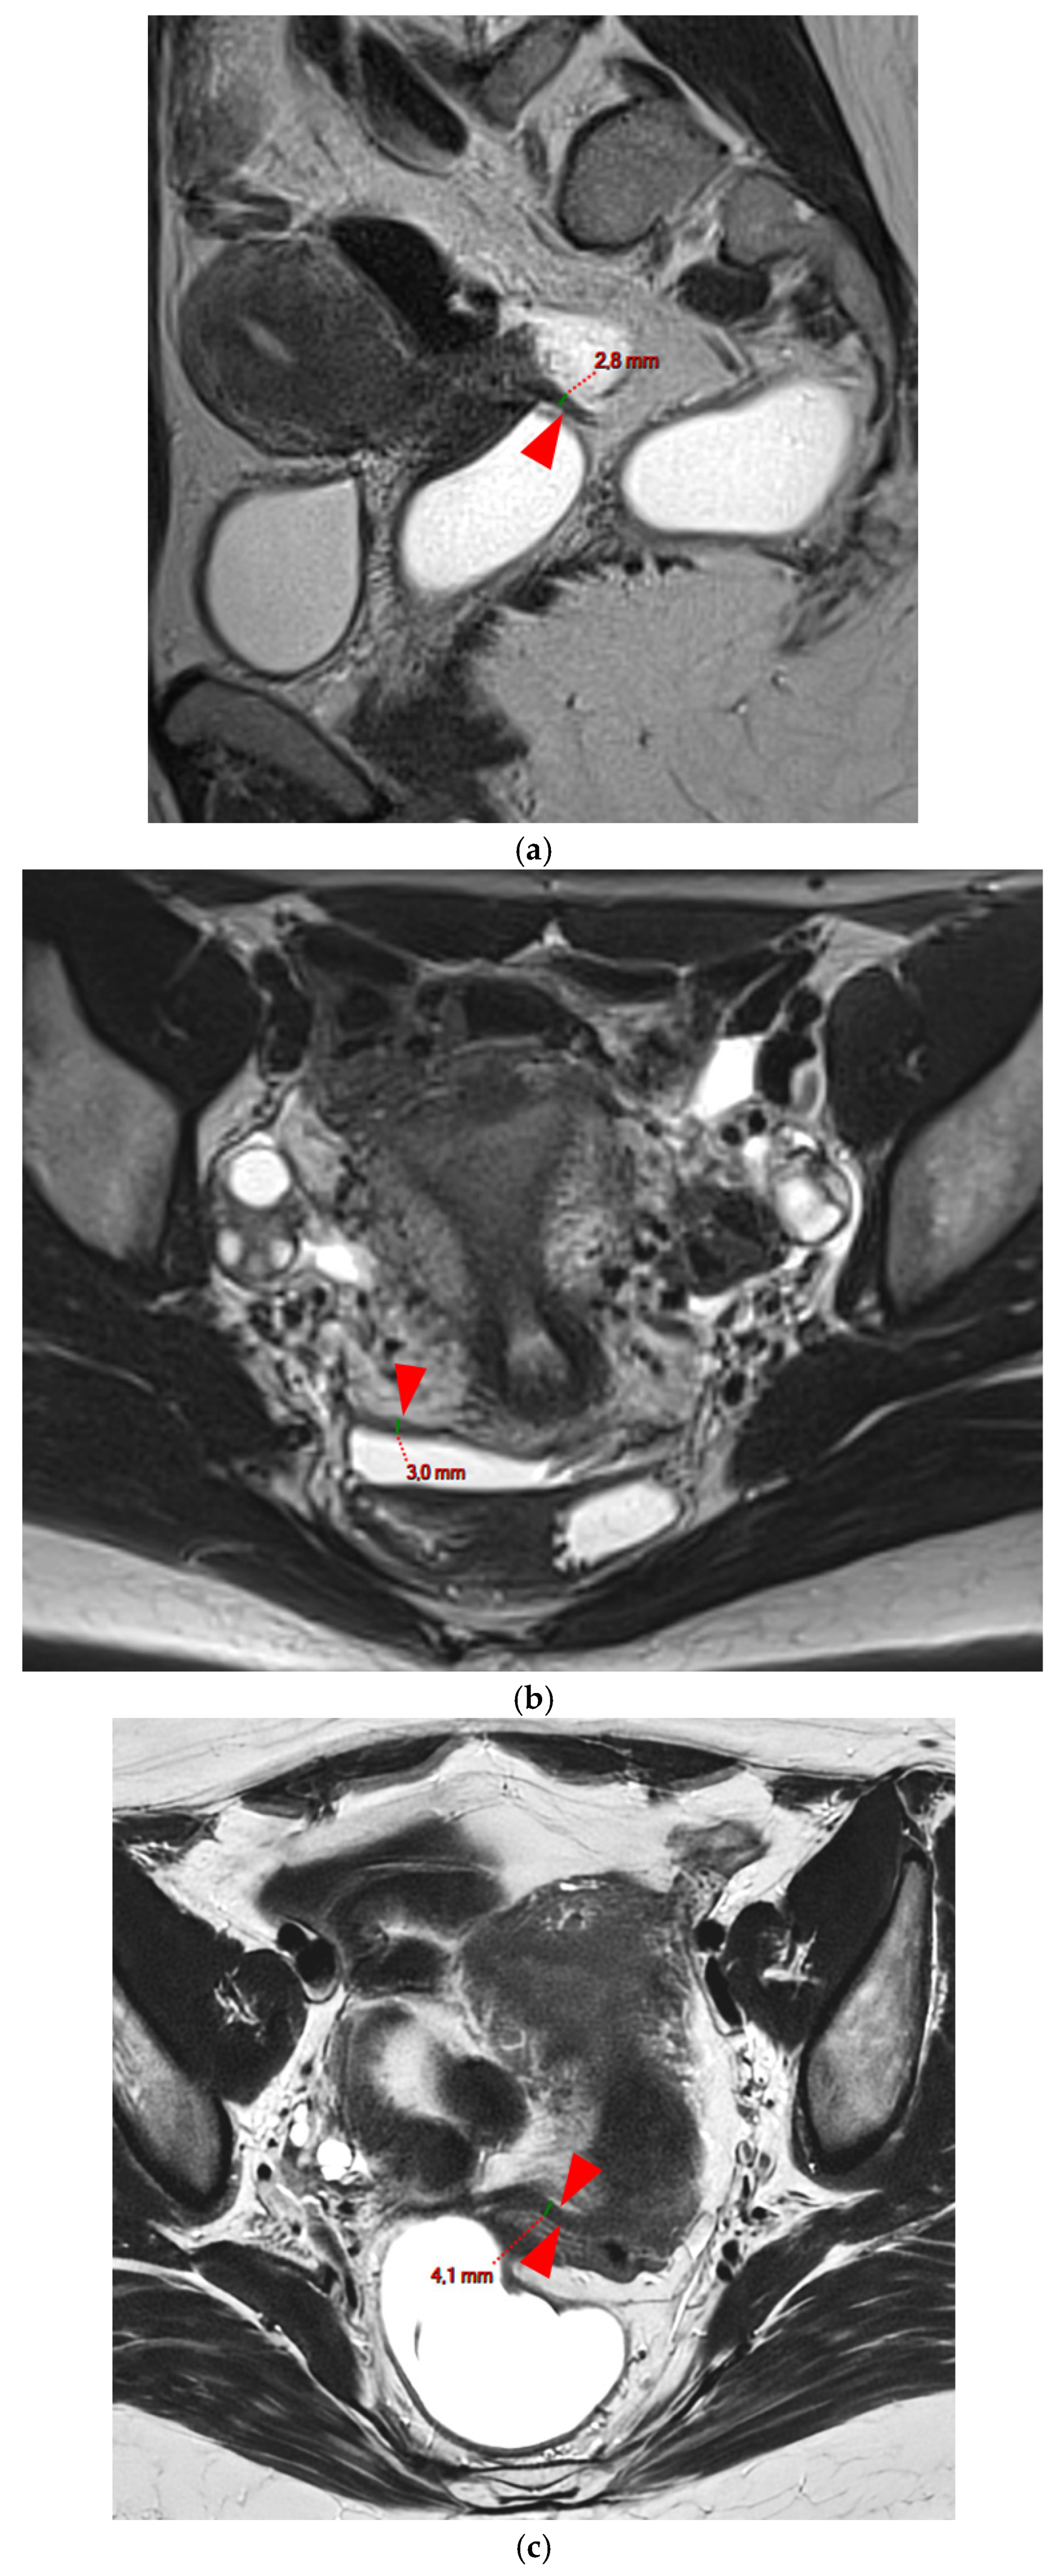

A type 3 USL appears as thickened (i.e., >2 mm), and can be classified either as type 3A (PPV = 75%; FPR = 25%) or as type 3B (PPV = 80%; FPR = 20%).

HTD Type 3A USL

A type 3A USL (Figure 3) maintains a smooth appearance with regular margins and often retains a tapering shape despite its thickening.

Figure 3. Pelvic MRI scans of three patients with thick (>2 mm), smooth, and regular USLs (HTD type 3A). (a) Sagittal T2WI: a thick (2.8 mm), smooth, tapering-shaped left USL (arrowhead). (b) Axial T2WI: regularly thickened (3 mm) right USL with a smooth surface (arrowhead). (c) Axial T2WI: regularly thickened (4.1 mm) right USL with a smooth surface (arrowheads).